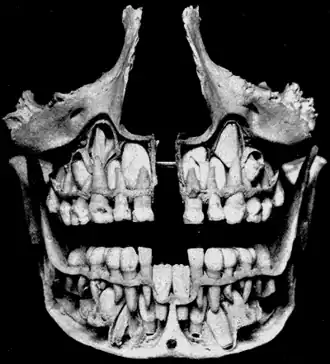

Base of skull. Inferior surface. Unerupted permanent teeth underlie the deciduous teeth.

Unerupted permanent teeth underlie the deciduous teeth.